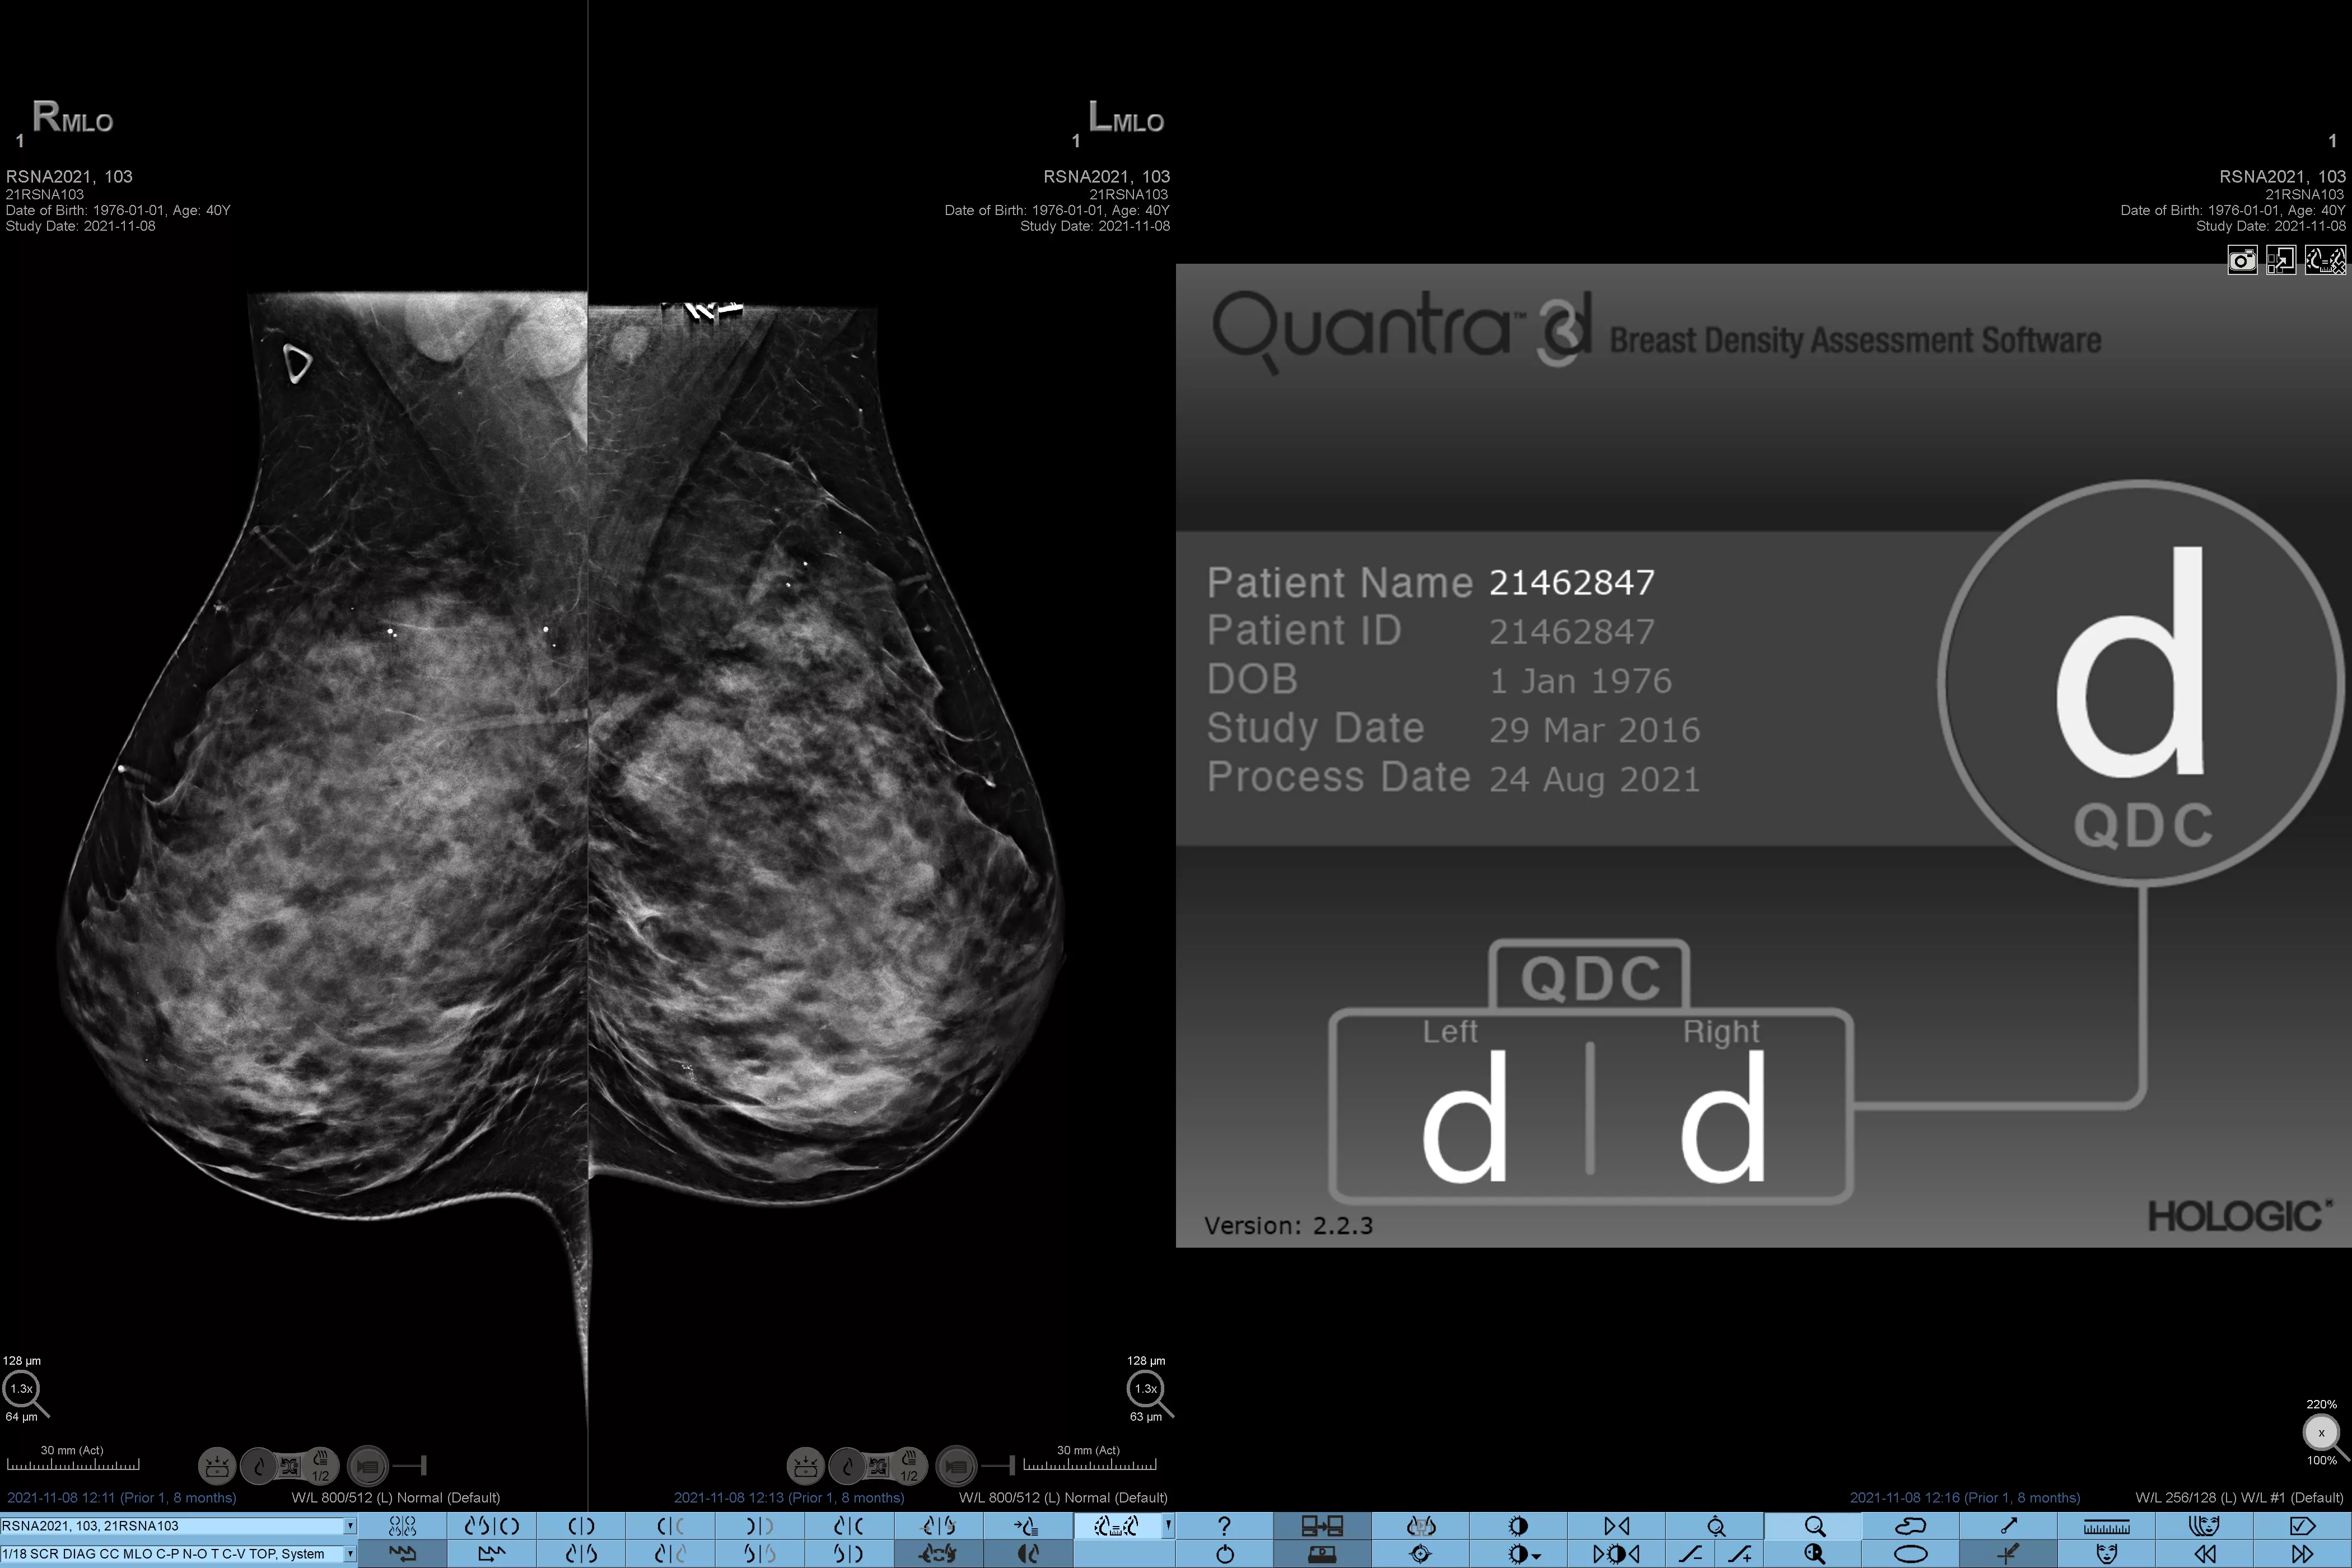

Higher breast density is known to increase a woman’s risk for breast cancer.1 The need for accurate, unbiased analysis is therefore critical. Powered by machine learning, Quantra technology software analyses both 2D™ and tomosynthesis images for distribution and texture of parenchymal tissue. It categorises breasts in four breast composition categories consistent with guidance from the American College of Radiology (ACR) BI-RADS Atlas 5th Edition.2

Objective machine learning algorithm that assigns breast density category based on analysis of breast tissue texture and patterns.